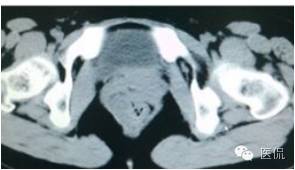

手术是:盆腔占位,病理为:血管肌纤维母细胞瘤。与肛门粘连,于是同时做了肛门的处理。